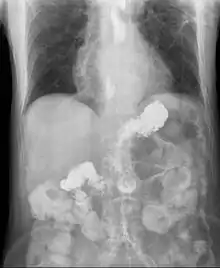

Gastroesophageal reflux disease (GERD), Gastro-oesophageal reflux disease (GORD), Gastric reflux disease, or Acid reflux disease is defined as chronic symptoms or mucosal damage produced by the abnormal reflux in the esophagus.[1]

This is commonly due to transient or permanent changes in the barrier between the esophagus and the stomach. This can be due to incompetence of the lower esophageal sphincter, transient lower esophageal sphincter relaxation, impaired expulsion of gastric reflux from the esophagus, or a hiatus hernia. If the reflux reaches the throat, it is called laryngopharyngeal reflux disease.